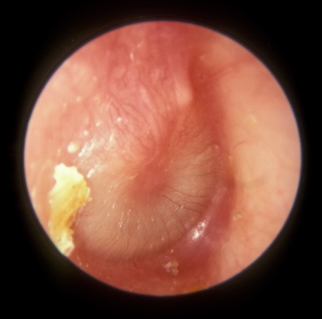

- Otoscopic signs:

- Bulging, erythematous tympanic membrane

- Fluid/pus behind drum

- Decreased mobility of the tympanic membrane